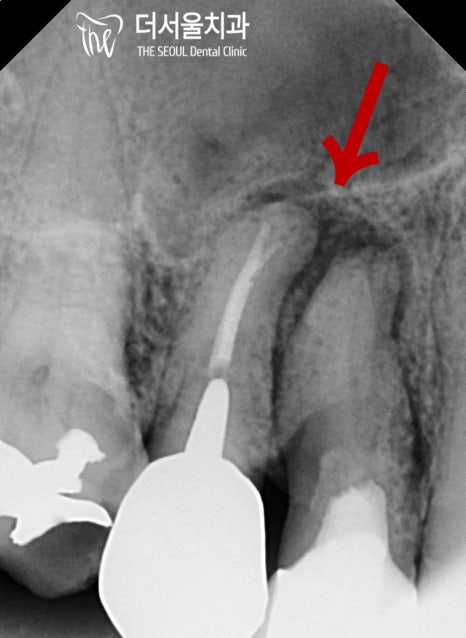

우선 정밀 검진을 통해

나타난 구강 문제를 확인해 보니

우측 어금니 거의 모든 곳에

염증이 나타나 있었습니다.

문제는 이런 곳이 한두 곳이 아니라는 것과..

병소가 생각보다 깊고 넓게 퍼져 있다는 것이죠.

표시해둔 곳을 보면 염증이 퍼져

치조골 소실까지 나타나 있는 곳도 있었습니다.